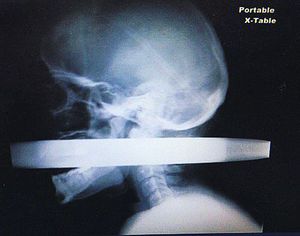

This patient was involved in a car crash after he fell asleep at the wheel and hit a fence.Luckily he survived after a 5cm-wide metal pole from that fence impaled him through his mouth and out the back of his head. The medical team at the scene was able to remove the pole without damaging either of two major blood vessels — the carotid artery and jugular vein — running close-by in his neck region.He made a full recovery with no paralysis!